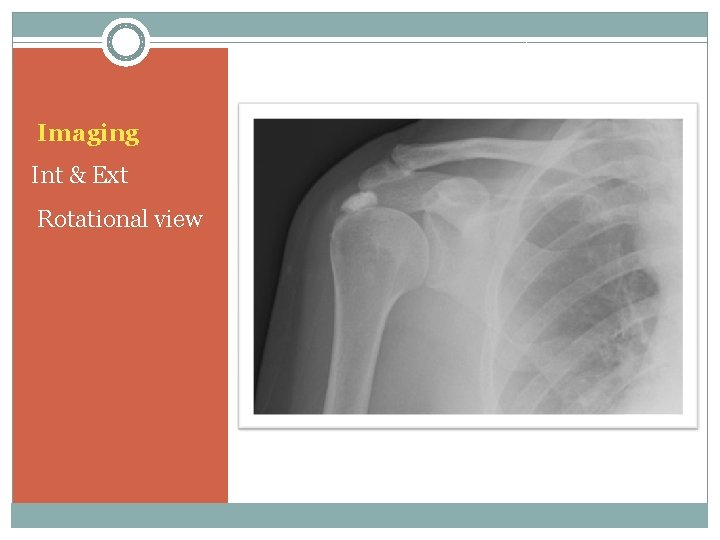

Imaging Int & Ext Rotational view